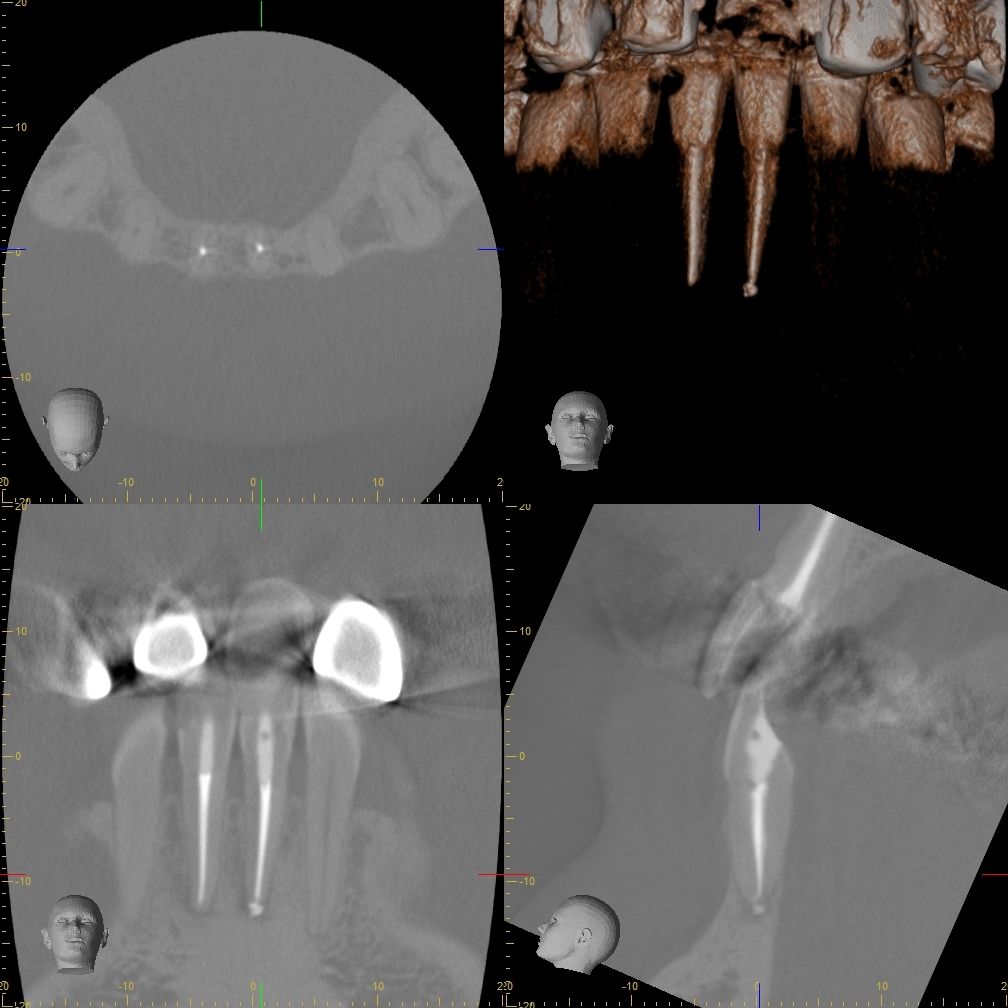

術前のレントゲン写真とお口の中の状態です。左上の前から6番目の歯(#26)です。

3本ある内の手前(近心)の根の中には治療用の器具が折れて残っていました。折れた器具が根管の中にあるだけでは問題になることは少ないですが、その先に感染がある場合は取り除いて治療をすることが望ましいです。

歯根の中の画像です。折れて残っている器具が確認できます。

超音波の器具を用いて取り除いていきます。今回は無事に取り除くことができました。

もし、根管内から取り除くことが困難な場合は外科的に対応していく場合もあります。

取り除くことが第一の目的ではないので、根管内の治療を進めていきます。

根の中を詰めた直後のレントゲン写真です。